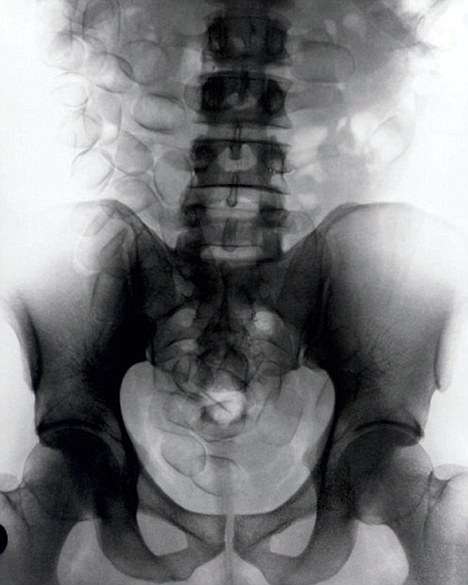

現(xiàn)年30歲的菲達(dá)利斯(Fidelis Ozouli)冒著生命危險(xiǎn)將重達(dá)1公斤的毒品吞下,被抓后卻辯稱(chēng)不知道吞下的是毒品。當(dāng)時(shí),曼徹斯特機(jī)場(chǎng)的海關(guān)人員看到毒販菲達(dá)利斯臃腫的肚腩,顯得很不自然,于是開(kāi)始懷疑。檢查人員用X射線機(jī)照他的胃部時(shí),發(fā)現(xiàn)了大量可卡因。目前他已被送往附近醫(yī)院,以確保排出所有的毒品。